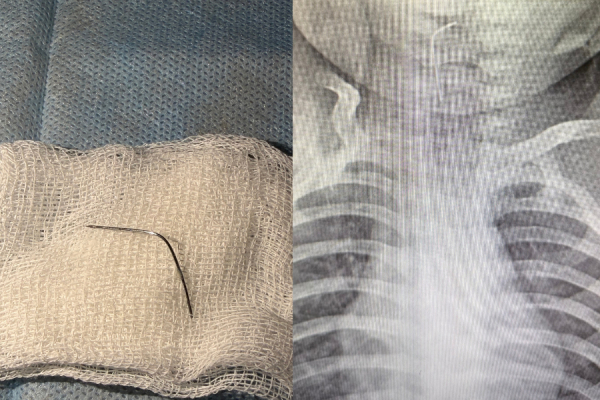

"Сәби абайсызда ине жұтып қойған. Дәрігерлер дереу рентгенологиялық тексеріс жүргізіп, бөгде заттың нақты орналасқан орнын анықтады. Түркістан облыстық балалар ауруханасының мамандары — хирург Мұхағали Темірбеков пен эндоскопист Бабыр Ырысқұлов өңеште тұрып қалған инені алды", — деп жазылған хабарламада.

Қазір баланың жағдайы жақсы. Сәби дәрігерлердің бақылауында болып, кейін үйіне шығарылған.